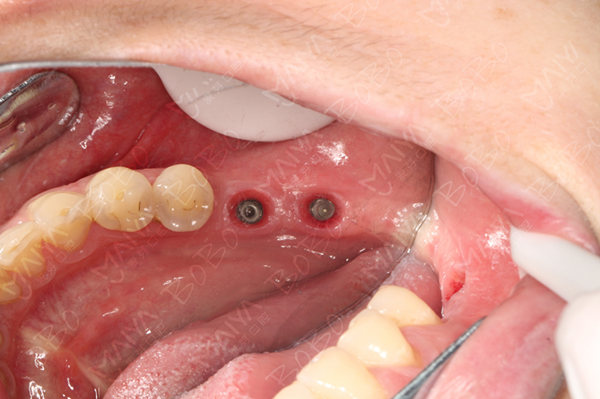

种植体的植入

"手术前非常紧张,即使工作人员一直很温柔的不断提醒我,但我仍止不住的害怕,开始手术后,工作人员非常细心,每一个步骤都仔细认真的讲解给我听,手术真的不觉得的痛疼,而且手术很快就结束了,术中没有任何的不适,原来种牙这么轻松,没有任何不适感。"术后郭女士高兴的说道。